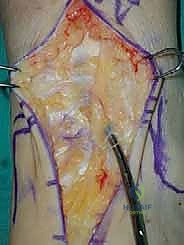

3. إزالة النتوءات العظمية وتحضير المفصل (Debridement)

بمجرد كشف المفصل، يقوم الجراح بإزالة الغشاء الزلالي الملتهب والزوائد العظمية (Osteophytes) التي تعيق الحركة. هذه الخطوة ضرورية لاستعادة المعالم التشريحية الطبيعية قبل إجراء القطع العظمي.

4. وضع أدلة القطع (Jig Placement and Alignment)

تعتمد دقة الجراحة على المحاذاة الصحيحة. يتم استخدام أجهزة توجيه متطورة (Jigs) تثبت على عظمة الساق باستخدام دبابيس معدنية. يتم التحقق من صحة الزوايا والمحاور باستخدام جهاز الأشعة السينية المباشر داخل غرفة العمليات (C-arm Fluoroscopy). يضمن الدكتور هطيف أن يكون القطع موازياً للأرض تماماً عند وقوف المريض.